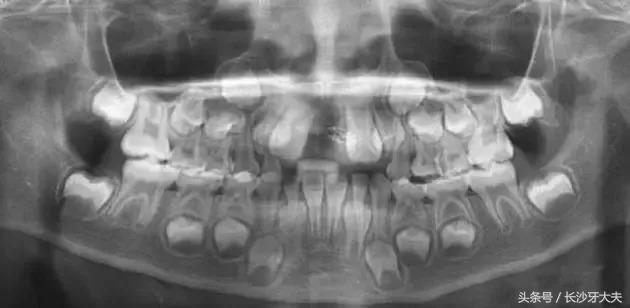

讲了这么多,给大家看一例真实的案例吧:由于多生牙占据了正常门牙应在的位置,两颗门牙还没长出来就被迫分开了很大的距离。

只有去除多生牙的阻碍,以后才可以进行矫正排齐门牙,所以我还是摆脱不了被拔除的命运。